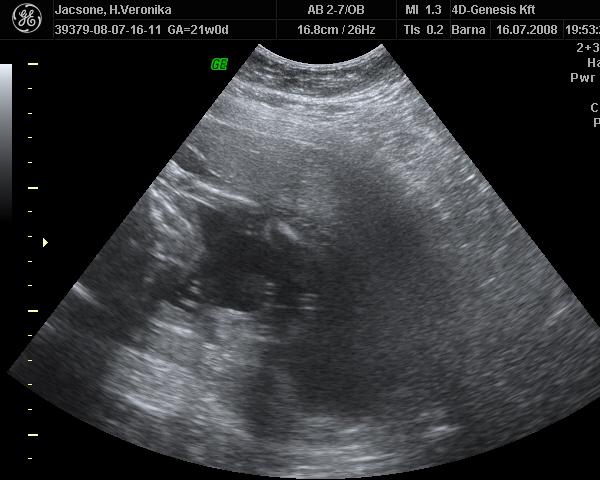

az hogy tényleg lány e már csak a szülésnél fogom megtudni mert a köldök zsinórt a lába közé rakta totáll és azt nem fogja onnan tudni kibűvészkedni már. De nem baj.

képek akkor tovább

Kép